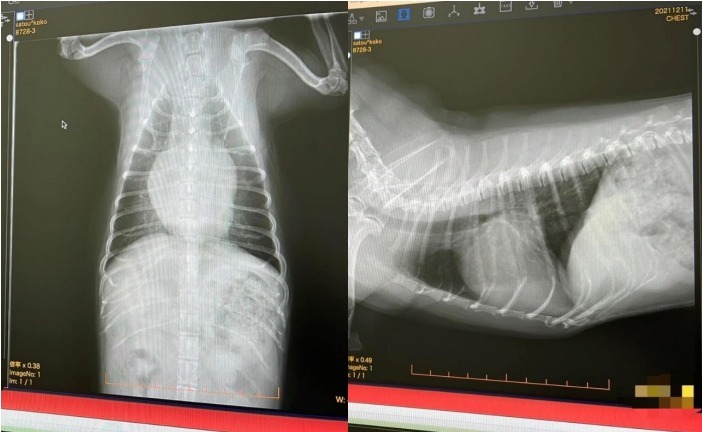

▼レントゲン写真

1月に一旦数値が落ち着いていたので主治医の先生と相談してもう少し様子を見ることになりましたが、3月にまた数値が上がり、やはり手術を検討した方が良いとの話になりました。